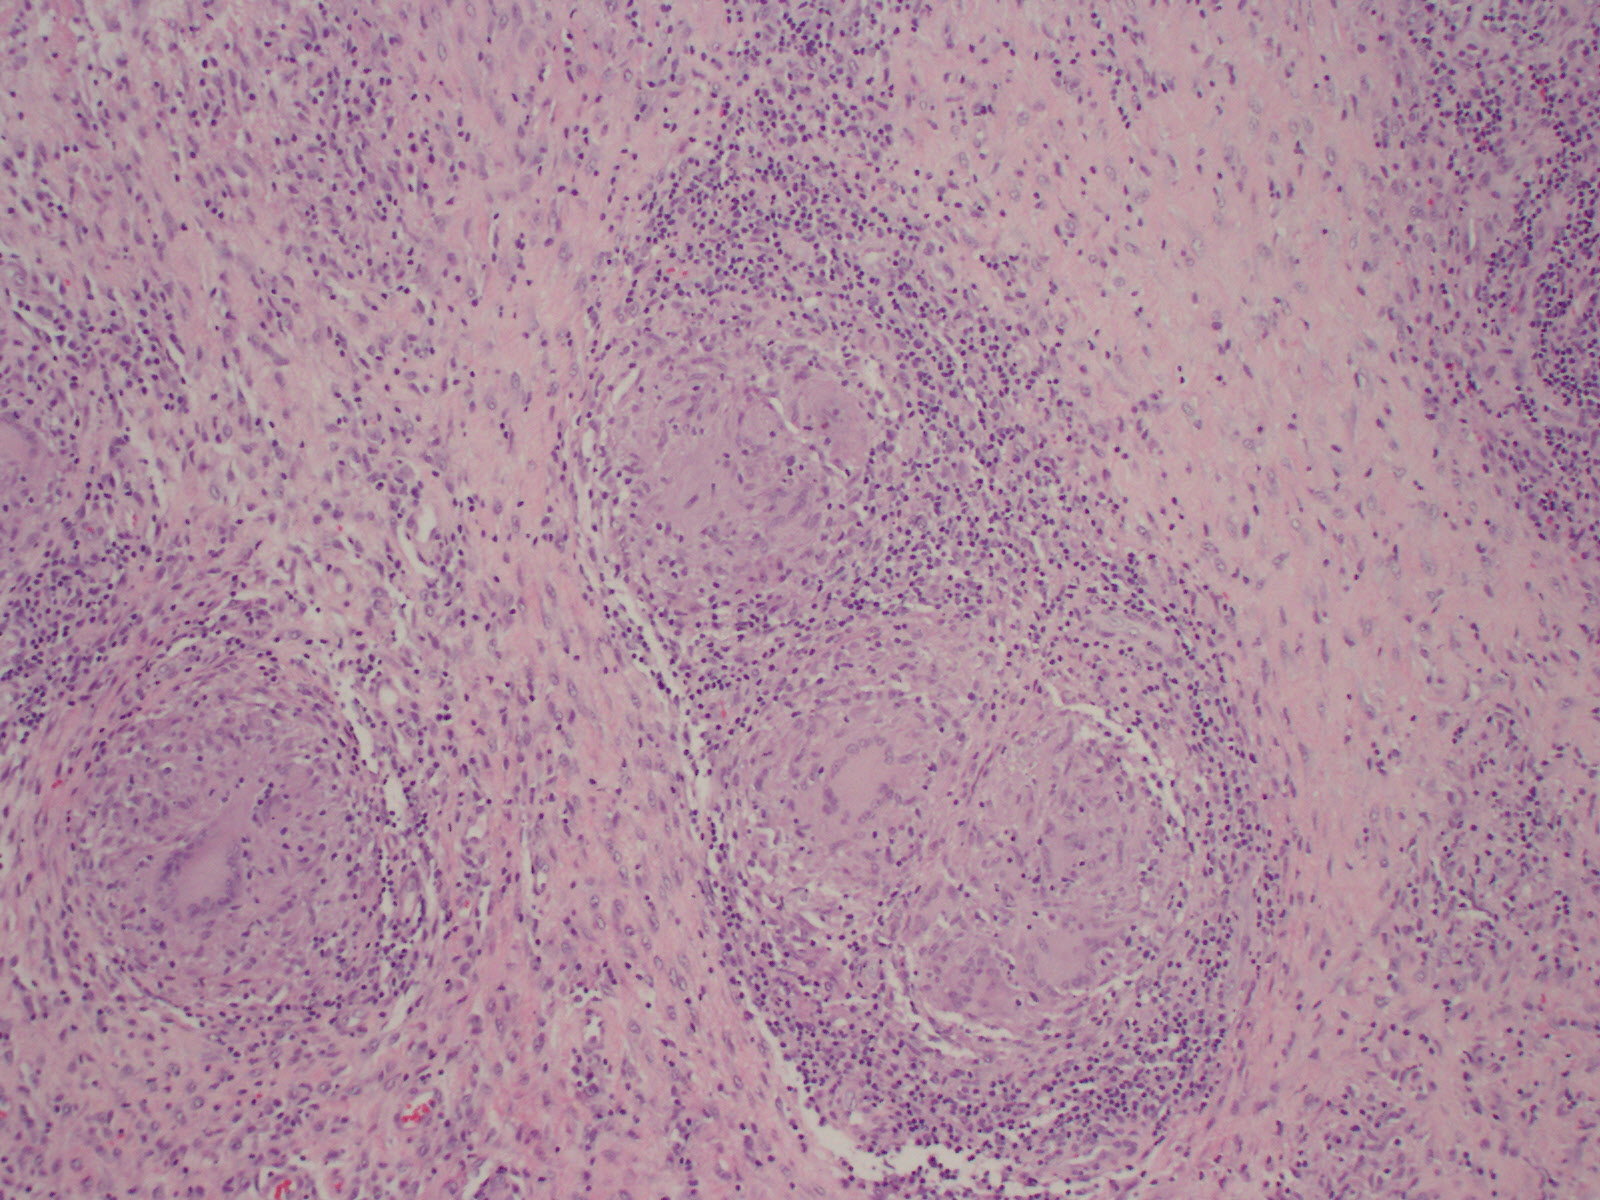

In September 2020, surgical debridement with contracture release was performed. Specimens collected during the procedure demonstrated positive histopathology with reactive bone and granulomatous findings (Figure 2). Results of an acid-fast stain of collected samples were negative. However, a mycobacterial culture with DNA probe returned positive results. Susceptibility was also tested, which demonstrated unsuppressed results for rifampin, isoniazid, pyrazinamide, and ethambutol.

Figure 2. Histopathology of an elbow bone specimen collected during surgical debridement demonstrated reactive bone and granulomatous findings.